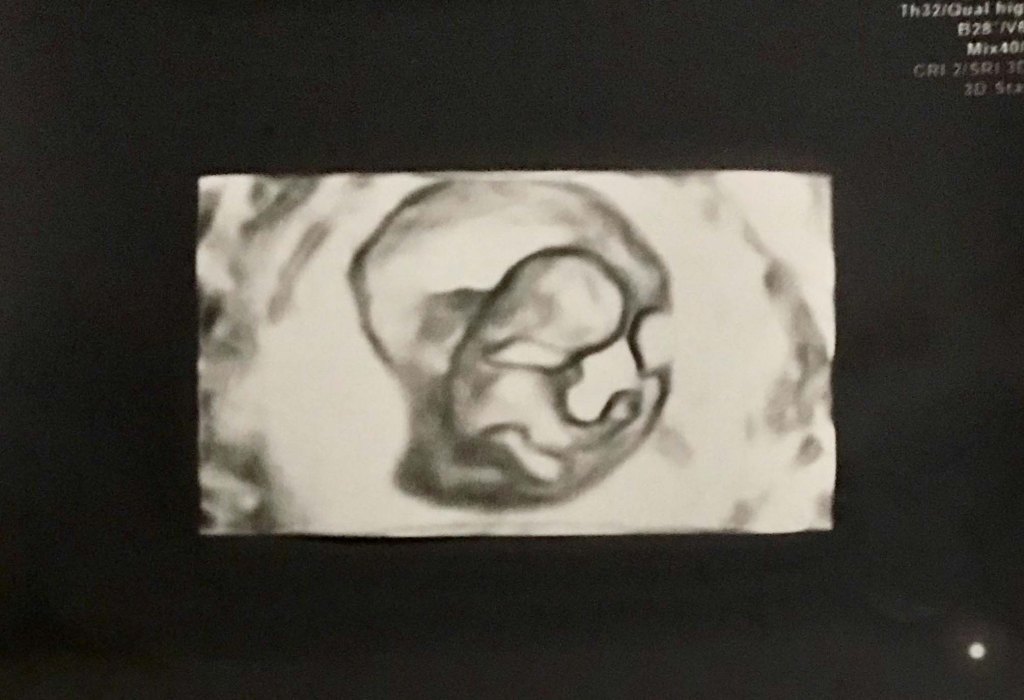

I do not know when the spirit enters the body in the womb. I do know I could see my little one twisting and wiggling on both 2D and 3D ultrasounds at 11 weeks (first trimester), and then the ultrasounds at 20 weeks (halfway through pregnancy) showed even more of her clearly human body, active and curious. Now, I feel her every day, playing, pushing, and punching away at my insides (making me need to pee all the time!).